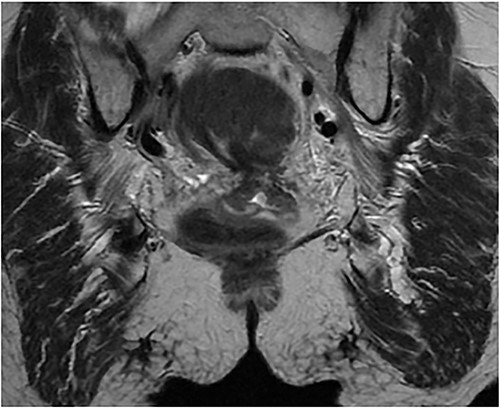

On hospital Day 2, patient underwent diagnostic sigmoidoscopy. We identified a bulky mass obscuring the lumen at 5 cm from the anal verge (Fig. 3). During hospital Day 3, patient was tolerating a clear liquid diet. A 1.5 Tesla Pelvic MRI demonstrated an apple core lesion, staged at least mT3N0, sparing anal sphincters, as shown in Fig. 4. Biopsy pathology identified adenocarcinoma. During hospital Day 4, oncology was consulted and recommended neoadjuvant chemoradiation therapy as outpatient.

1.5 pelvis MRI, coronal view demonstrates apple core lesion at 5 cm from anal verge staged at T3N0 without involvement of anal sphincter.